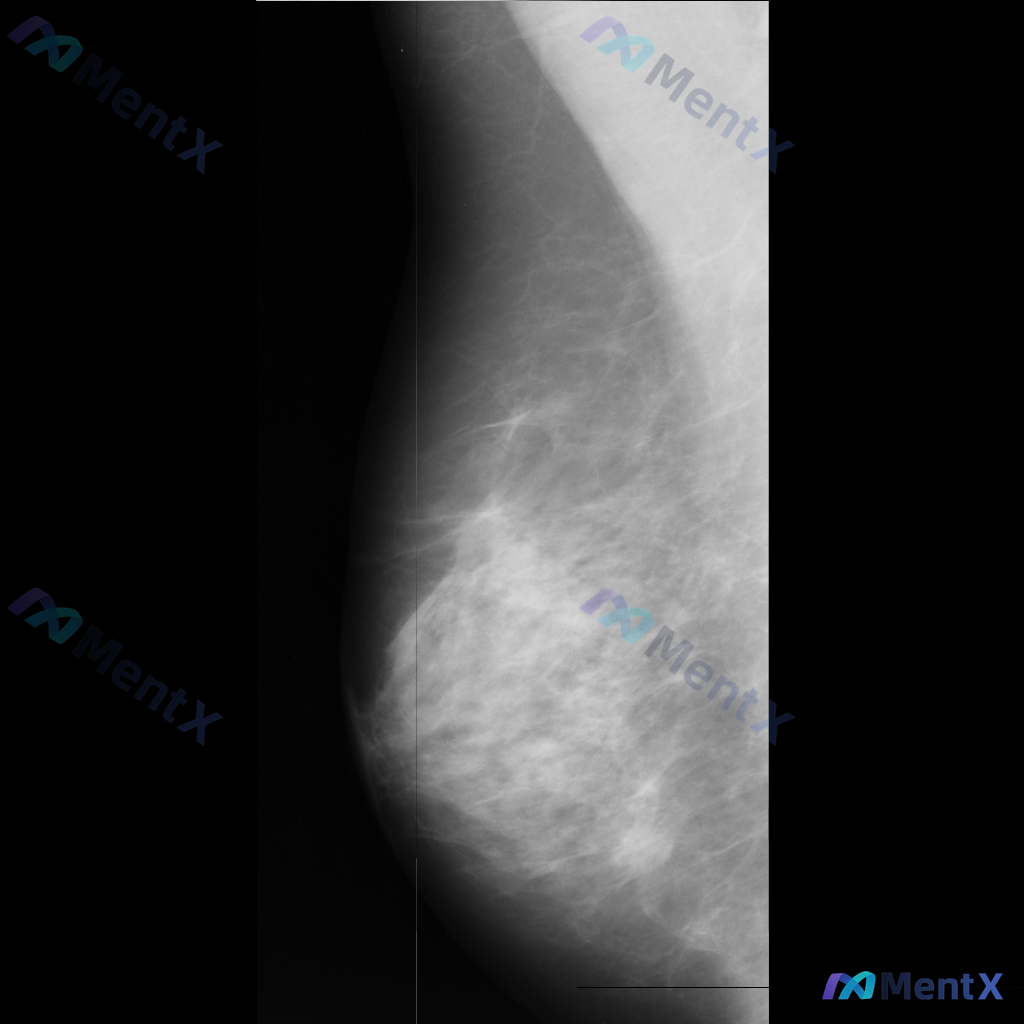

这张乳腺钼靶影像里的异常表现,大家更倾向哪种可能性?

影像里能看到的主要异常是乳腺内结构扭曲(正常导管小叶结构有集中、牵拉、不规则向中心汇聚的表现,但没有明确肿块),同时还有不对称致密影(局部组织密度增高,和周围或对侧分布不太一致)。另外,乳腺本身纤维腺体组织偏多,可能属于 BI-RADS c/d 类致密型乳腺;目前只有单侧这一张影像,没有双侧对比或既往片可参考。

想请教大家:单从目前这张影像的表现来看,你第一反应会更倾向哪一类情况?后续如果要进一步明确,你会优先安排哪些检查?